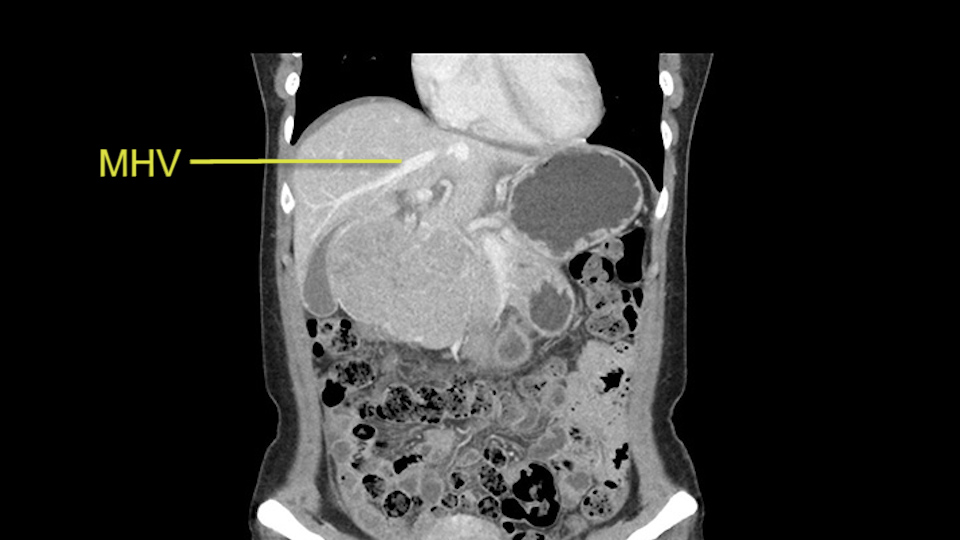

So if we look at the CT scan, on the axial, it’s a larger lesion. It’s about 6 or 7 or 8 centimeters. So it does look a bit threatening in terms of its resectability but if you really drill down deeply into the anatomy, and I think the coronal [imaging] is even better, you can see that the entire mass is on the patient’s left side of the falciform ligament. So it’s really only a left-sided tumor and not even really a left-sided tumor because Segment 4 is uninvolved anatomically.

Anatomically, to plan for a left lateral segmentectomy, it’s relatively easy as far as liver surgery goes. I know that I'm going to be looking for the left hepatic vein which will be divided at some point either towards the end at the back near the vena cava or through the middle of the left lateral segment.

So the issue with regards to resection. A left sided tumor. I believe I can see the falciform ligament right here so we’re looking at a resection of Segments 2, 3 of the left lobe of the liver. The left portal vein is right there. I think we’ll be wiser to take the left portal vein and therefore get well into Segment 4 and do a left hemihepatectomy. Certainly, one does not need to take the middle hepatic vein; it’s miles from the tumor.

The transection line will be a little more obvious. There’s a little patch of focal fat here in Segment 4b but we’ll describe the transection line probably through the mid portion of Segments 4a and b up to the top. Up at the top, the left hepatic vein can be taken. There’s a Segment 3 vein or the so-called falciform vein it’ll be rudimentary so I think we’ll be able to get around the left hepatic vein and leave the middle [hepatic] vein intact because it’s free of tumor.

Her vein, it looks like a combined middle and left hepatic vein, it may be encircled during the case as a whole common trunk but most probably it will not be a big deal because if it is okay to go with the left lateral resection, the vein or the left hepatic vein can be catched during the intraparenchymal dissection and can be controlled in that side.

The cava however is again displaced by this well encapsulated mass, so I would expect that I should be able to lift out of the cava with some moment of careful dissection and the cava is not infiltrated by this tumor. Most of the tumor is below the portal plane and the hepatic-venous vein is completely free. You have the left and the middle hepatic vein joining together and opening up. The right hepatic vein is as usual. All the superior segments of the liver are intact so we do not expect any major problem in this particular case as far as the venous outflow is concerned. So this is about the preoperative planning as far as this case is concerned.

The other thing I would do in this case is to certainly to assess the coronal phase as we can see in the coronal phase, this tumor looks like it's growing from Segment 3, and again I don’t think there’s involvement of the right side of the liver or even on Segment 4.

The other option of course is to do an anatomical left hepatectomy. In that case, I will start mobilizing of course the left lobe and try to find the ligamentum venosum, take it down and go around the left hepatic vein. I think, importantly in these cases and in this case, as you can see in the venous phase, that’s clearly a moment to stop. Because the left hepatic vein is pretty close to the middle hepatic vein as sometimes it is so you may need to dissect a little bit the parenchyma on top of the left hepatic vein to be able to go around the left hepatic vein safely.